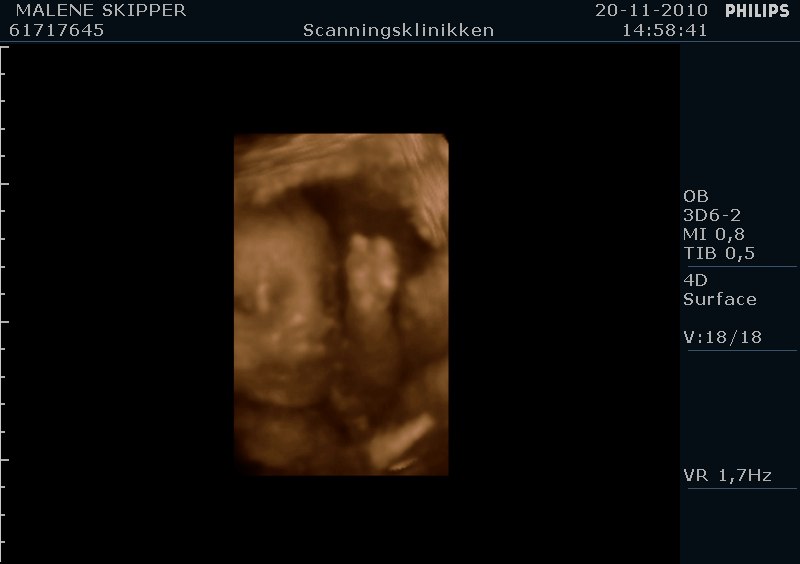

" /> Jeg har været til 4d scanning idag og set vores lille prinsesse som vi er meget stolte af og glæder os til hun kommer ud.. Hun sparker og er livlig hver dag og det er fantastisk..

Her er lige et par billeder fra 4d scanning idag..